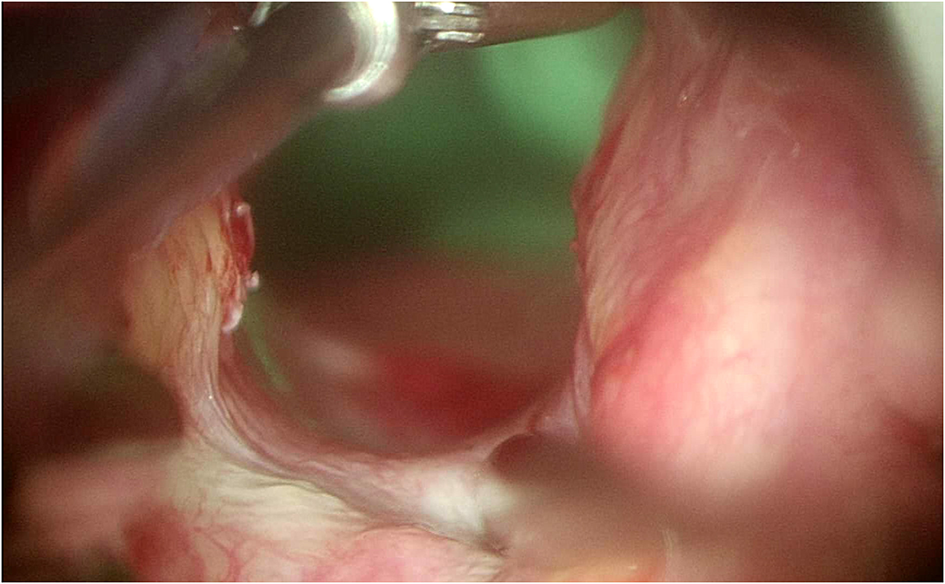

Once we had carefully assed the craniocaudal extension and the degree of the stenosis, differential diagnosis between BVCP and PGS is mandatory. Important information can be provided by the patient's medical history. Lindholm cord retractor and an angulated probe are used to precisely assess the posterior laryngeal commissure and cricoarytenoid joint function in all the patients who have previously undergone orotracheal intubation. The former is placed at the level of the vocal fold and is opened. In patients with neurogenic BVCP, the interarytenoid distance is restored to its normal size, while in patients with PGS it remains narrow, and a stretched band of scar tissue may be observed (Figures 7A,B).

Figure 7

(A,B) Lindholm cord retractor.